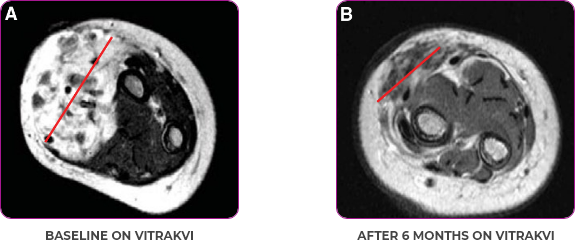

Reduction in tumor burden1

MRIa imagery of the brain. Red line indicates the maximum dimension.1

aMRI, magnetic resonance imaging.

Pre- and post-treatment imaging, by DuBois SG et al, is licensed under CC BY 4.0.

- Patient achieved a confirmed partial response after 4 cycles of VITRAKVI with a 45% reduction in tumor burden

- Following 6 cycles of VITRAKVI, the patient was referred for definitive limb-sparing surgery

- Pathology revealed a complete pathologic response and clear resection margins with scar tissue noted